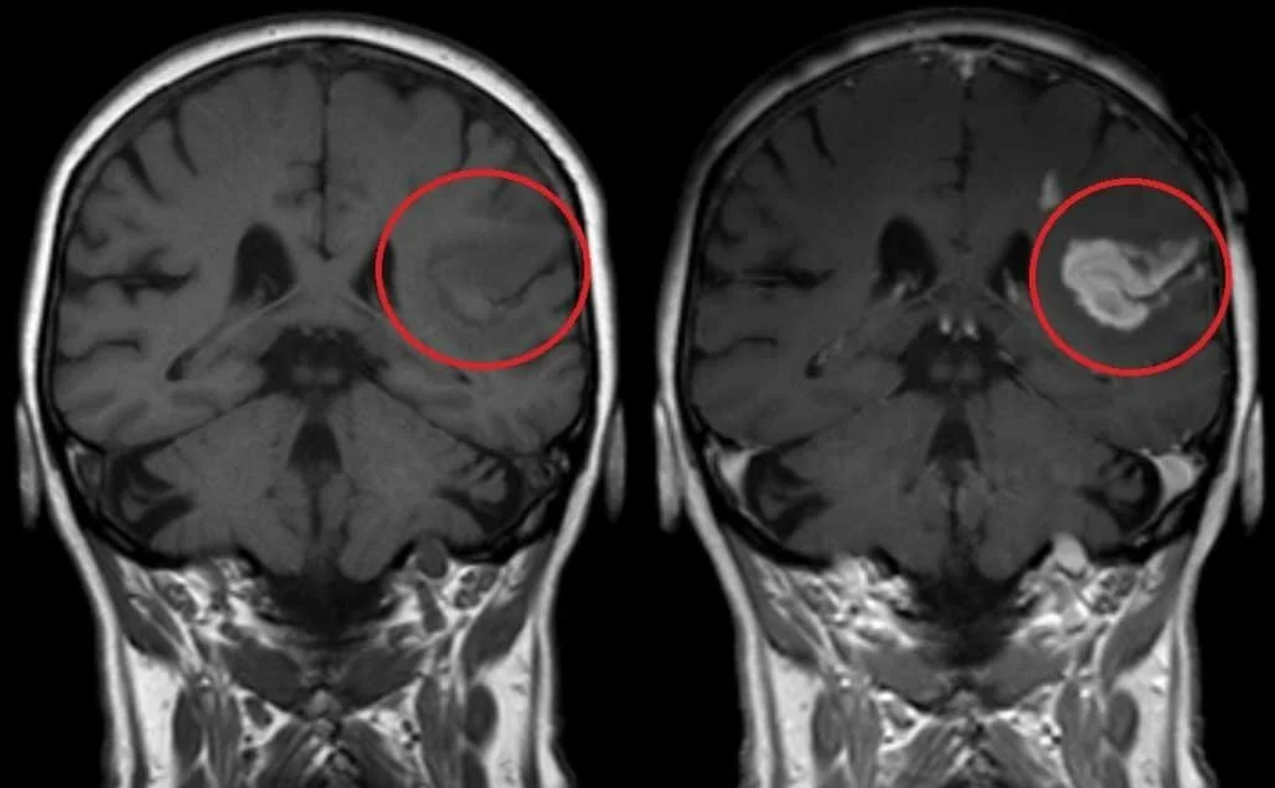

МРТ головного мозга: показания и результаты

Раздел: Визуальный дайджест